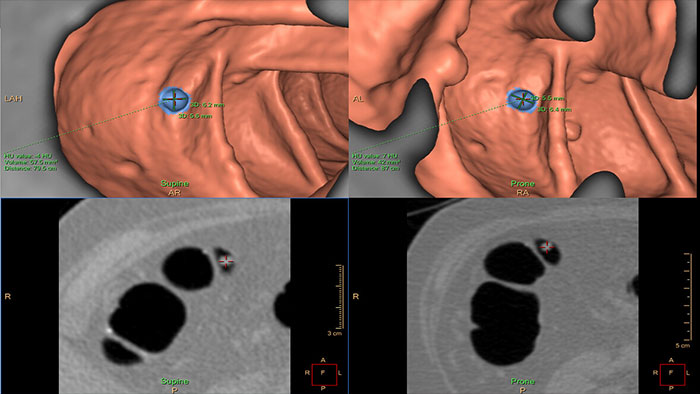

Assessing lung nodules over time

Enables review and analysis of thoracic CT images, providing segmentation, quantification and characterization of physician-indicated lung nodules. The application can be used in both diagnostic and screening evaluations, supporting Low Dose CT Lung Cancer Screening*

Benefits